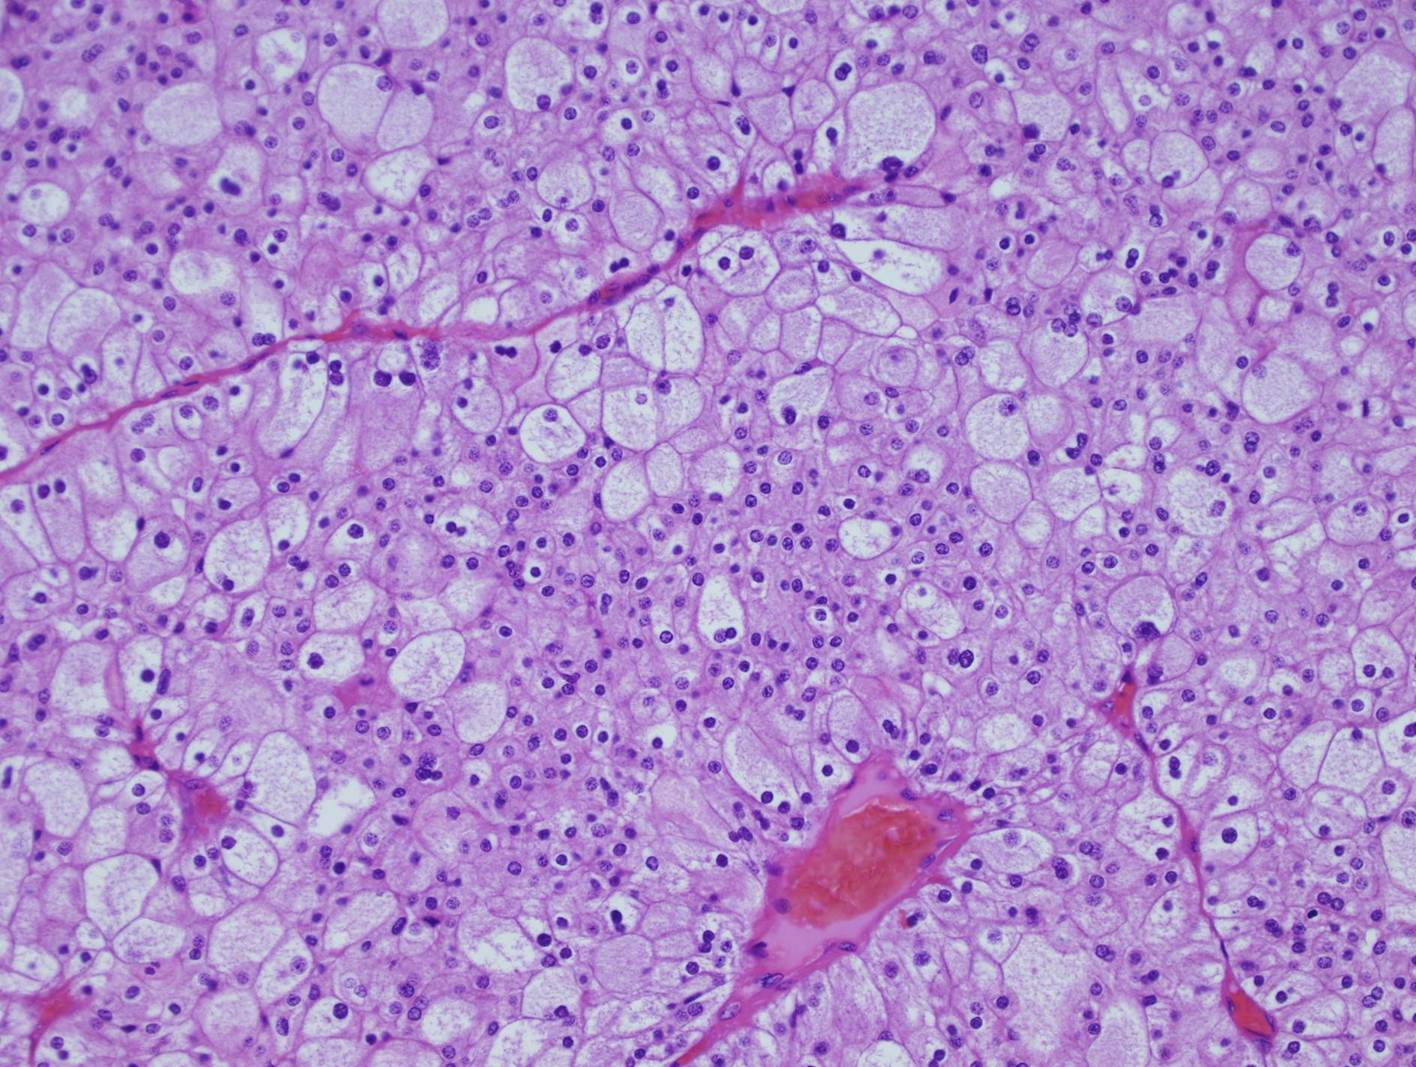

Classification of renal tumors

Case ID: 702